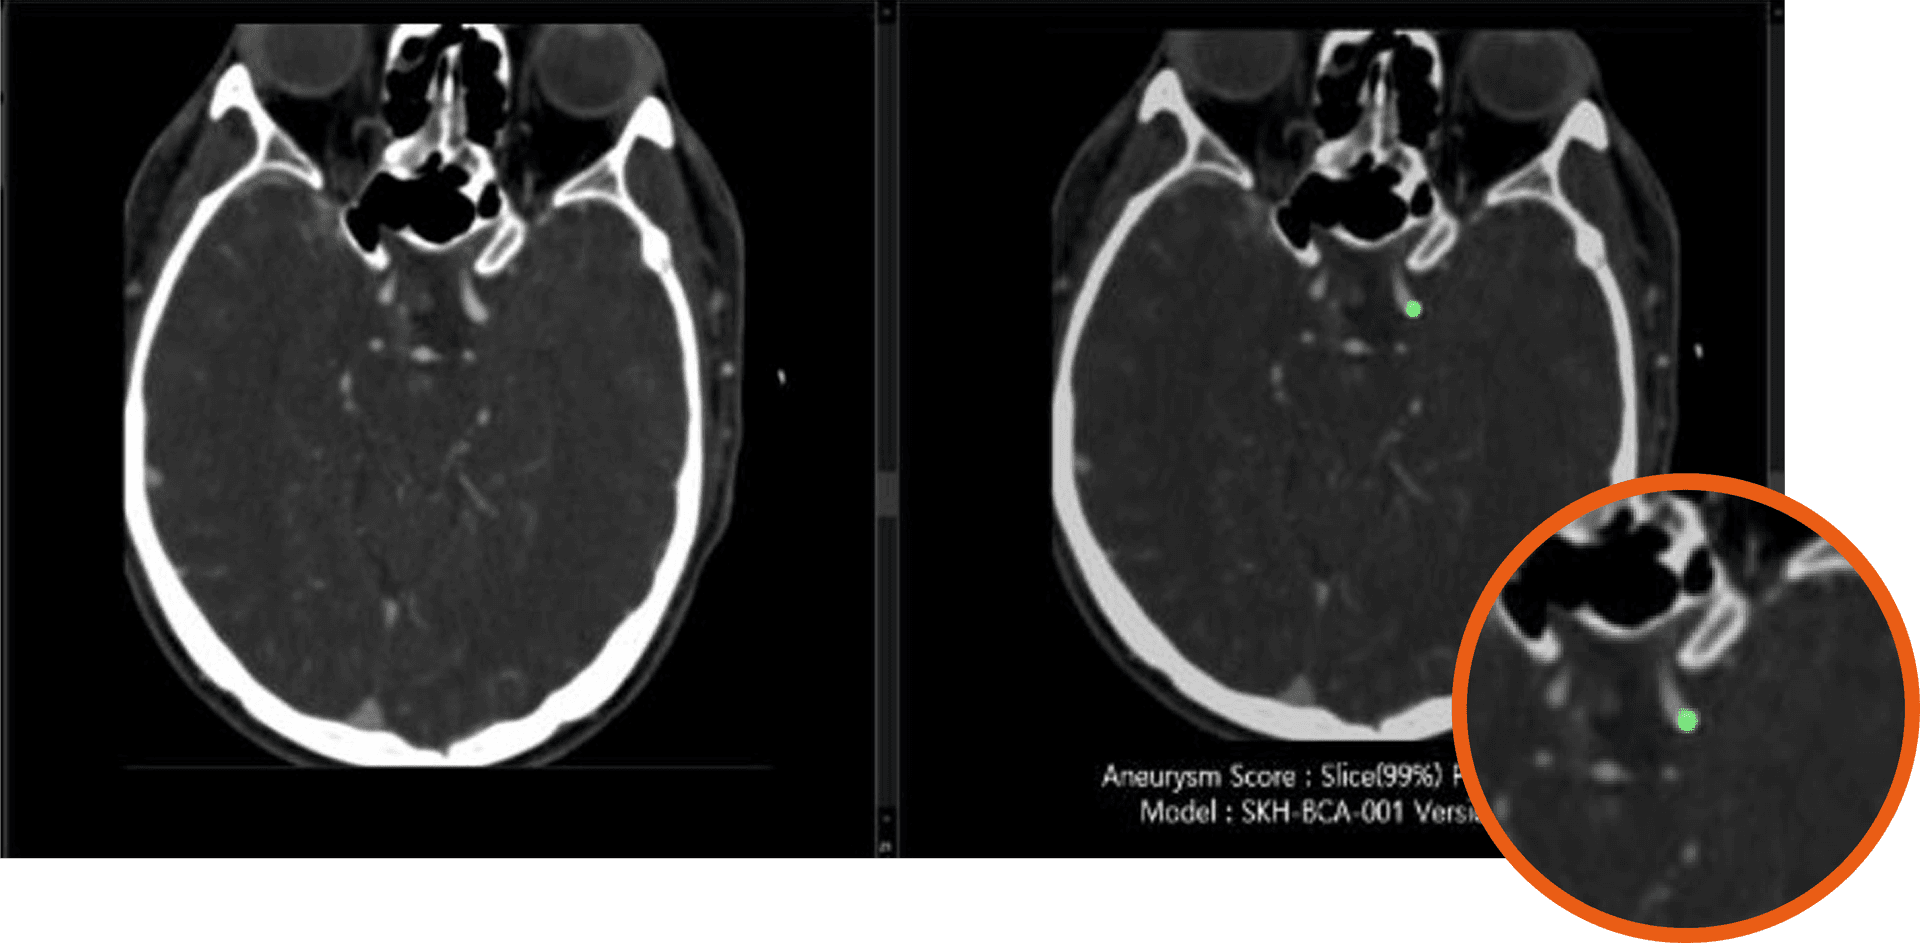

AI analyzes the scan and alerts you topatients with suspected brain hemorrhage.

AI clinical decision support (CDS) accelerates physician decision-making, but not all AI is created equal. The most advanced CDS tools go beyond basic detection—precisely identifying, analyzing, and quantifying suspected conditions with exceptional accuracy and speed.